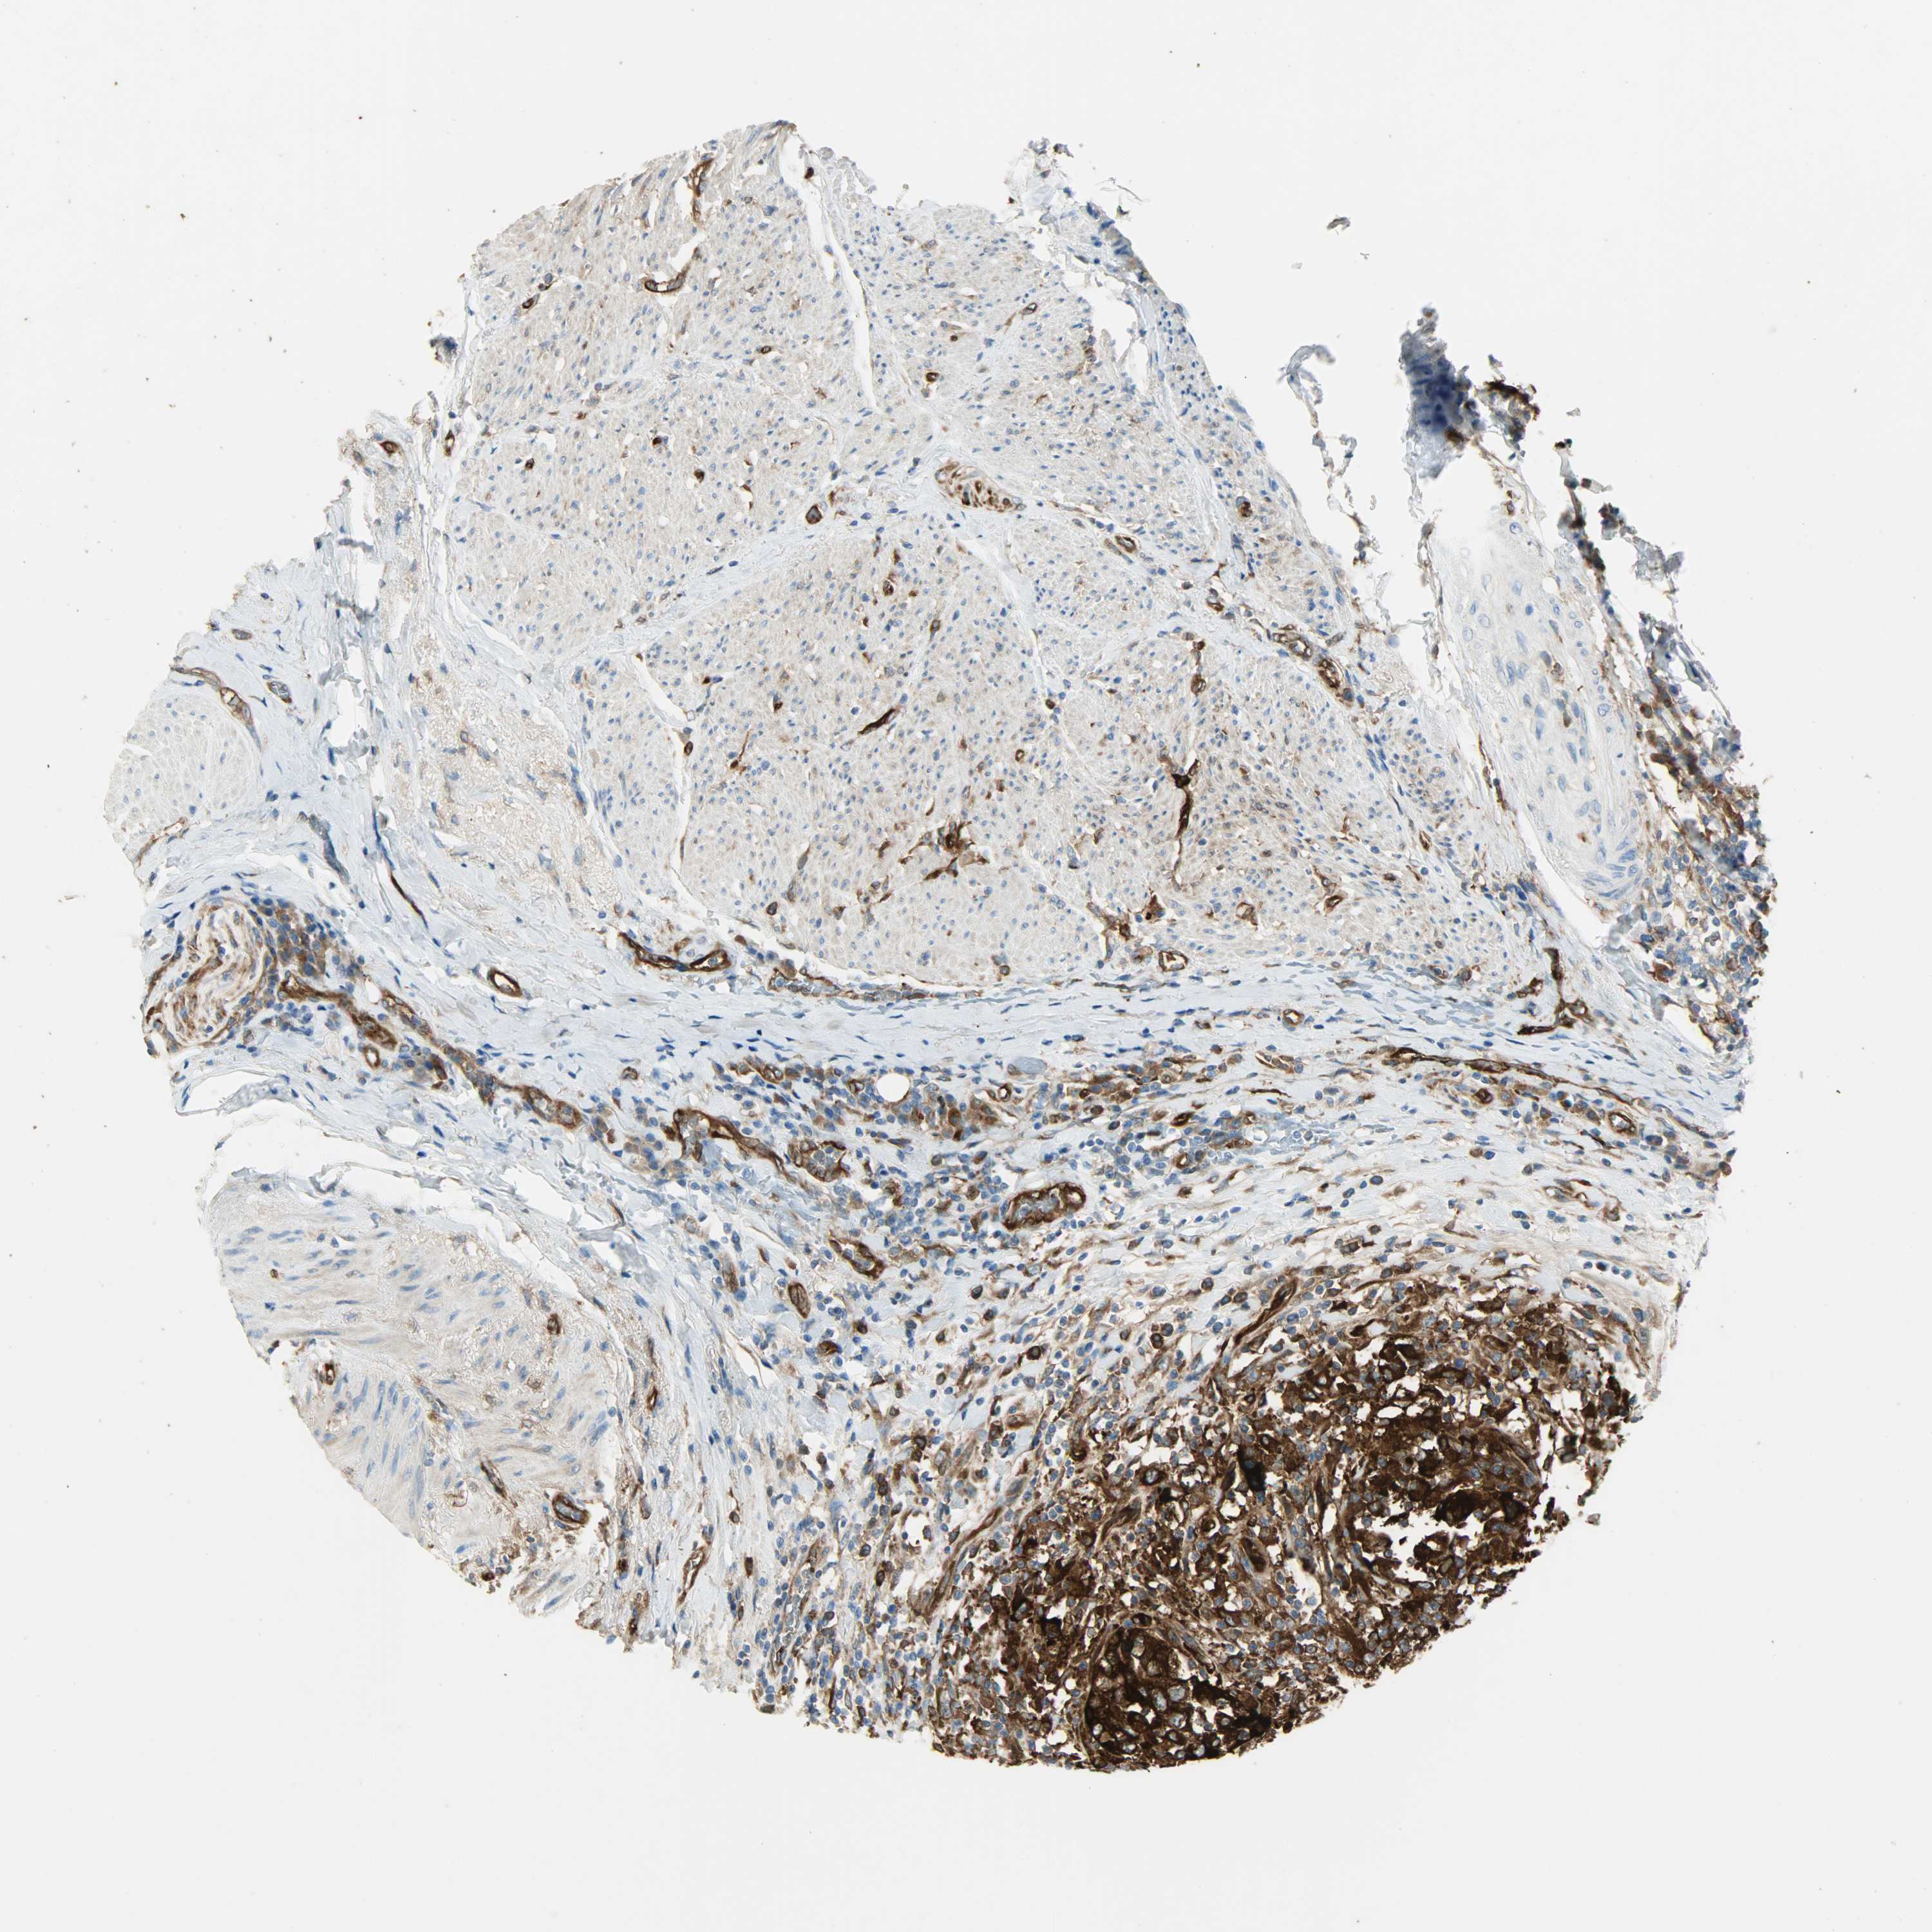

UROTHELIAL CANCER - Protein expressioni

A mouse-over function shows sample information and annotation data. Click on an image to view it in a full screen mode. Samples can be filtered based on level of antibody staining by selecting one or several of the following categories: high, medium, low and not detected. The assay and annotation is described here.

Note that samples used for immunohistochemistry by the Human Protein Atlas do not correspond to samples in the TCGA dataset.

Antibody stainingi

Antibody staining in the annotated cell types in the current human tissue is reported as not detected, low, medium, or high, based on conventional immunohistochemistry profiling in selected tissues. This score is based on the combination of the staining intensity and fraction of stained cells.

Each image is clickable and will lead to virtual microscopy that enables deeper exploration of all samples and also displays staining intensity scores, fraction scores and subcellular localization as well as patient and tissue information for each sample.

Antibody HPA005573

Staining

High

Medium

Low

Not detected

Intensity

Strong

Moderate

Weak

Negative

Quantity

>75%

75%-25%

<25%

None

Location

Nuclear

Cytoplasmic/membranous

Cytoplasmic/membranous,nuclear

Urothelial carcinoma, High grade

Urothelial carcinoma, Low grade